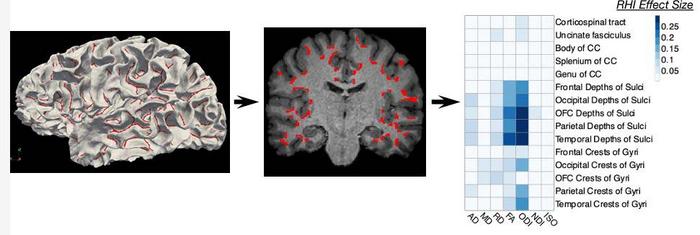

Diffusion MRI shows the effect of soccer heading on brain regions. RHI = repetitive head impacts

While prior studies have identified injuries to the brain’s white matter in soccer players, Dr. Lipton and colleagues utilized a new approach to an advanced brain imaging technique called diffusion MRI to analyze microstructure close to the surface of the brain.

Soccer players who headed the ball at high levels showed abnormality of the brain’s white matter adjacent to sulci, which are deep grooves in the brain’s surface. Abnormalities in this region of the brain are known to occur in very severe traumatic brain injuries.

The abnormalities were most prominent in the frontal lobe of the brain, an area most susceptible to damage from trauma and frequently impacted during soccer heading. More repetitive head impacts were also associated with poorer verbal learning.

“Our analysis showed that the white matter abnormalities represent a mechanism by which heading leads to worse cognitive performance,” Dr. Lipton said.